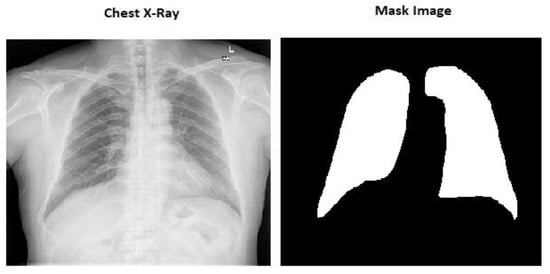

The X-ray pictures for this dataset came from the Department of Health and Human Services’ TB control program in Montgomery County, MD, USA. This dataset contains 138 X-ray images, out of which 80 are in the normal category, and the remaining data are in the tuberculosis infection category. All the pictures are in DICOM format and have been de-identified. Among the oddities in the collection are effusions and militaristic motifs [13].

The mask pictures are included in all the chest X-ray images in the dataset. There are 800 chest X-ray pictures and 704 mask images in all.

Here in Figure 1 we can see the image size is (256 × 256 × 3) which is the actual size of the image and Figure 2 is the modified image which is (256 × 256 × 1).